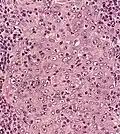

Micrograph showing a nasopharyngeal carcinoma positive for Epstein-Barr virus-encoded small RNAs (EBER).